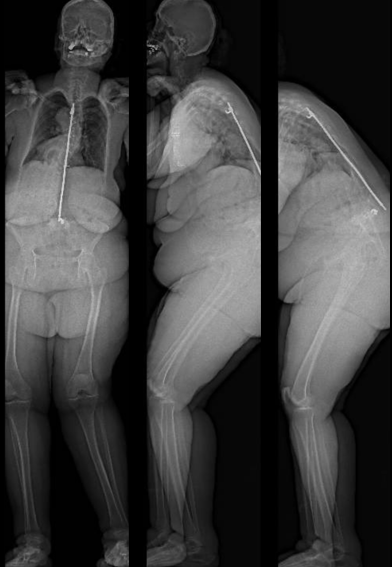

Severe malalignment case: Performed T12-S1/Pelvis posterior instrumentation, TLIF at L5-S1 & L5 PSO. No anterior approach on vascular team's advice. Patient now stands upright & grateful. #SpineSurgery #MedTwitter #scoliosis #flatback #HarringtonRods #ScoliosisWarrior

10

50s patient with severe malalignment. How would you treat this surgically? Nnee compensation in coronal and sagittal planes. Options: Multisegment instrumentation, TLIF/ALIF/OLIF, PSO, refer to another surgeon? Thoughts? #neurosurgery #spine #scoliosis #flatback #harringtonrods